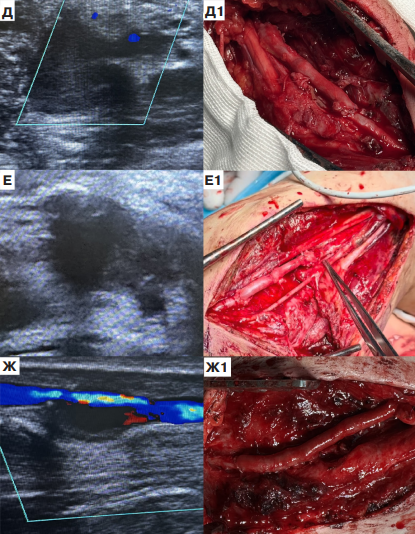

Оперативное лечение псевдоаневризмы плечевой артерии

На рисунке 2 слева представлены ультразвуковые снимки псевдоаневризмы плечевой артерии до вмешательства, справа — результат оперативного лечения в объеме аутовенозного протезирования реверсированной БПВ. Относительно предыдущей группы больных, техническая сторона операции облегчалась более поверхностным топографическим расположением сосудов. В остальном наблюдались аналогические особенности — рубцовые изменения тканей, близкое расположение нервных структур.

Рис. 2. Оперативное лечение псевдоаневризмы плечевой артерии.

Примечание: Д, Е, Ж — снимки УЗИ плечевой псевдоаневризмы 1, 2, 3 пациентов до операции, соответственно; Д1, Е1, Ж1 — удаление псевдоаневризмы с аутовенозным протезированием плечевой артерии у 1, 2, 3 пациентов, соответственно.